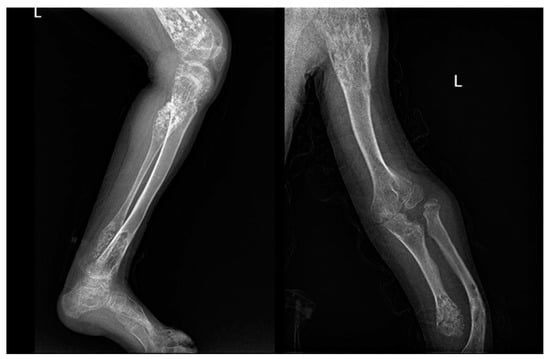

Figure 2. X-rays of multiple osteochondromas.

3.1.5. Imaging

At X-ray examination, osteochondroma is usually localized in the metaphysis, and its cortex is in continuity through a marrow cavity with the originating bone cortex. In the case of symptomatic patients, further investigations could be necessary with MRI, CT, or US. MRI is helpful to evaluate the cartilage cap and bone thickness in adults and the possible complications, such as bursae, neurological, and vascular involvement [59]. Scintigraphy shows enhancement in benign and malignant lesions; for this reason, it is not a valuable test for diagnostic purposes (Figure 2).